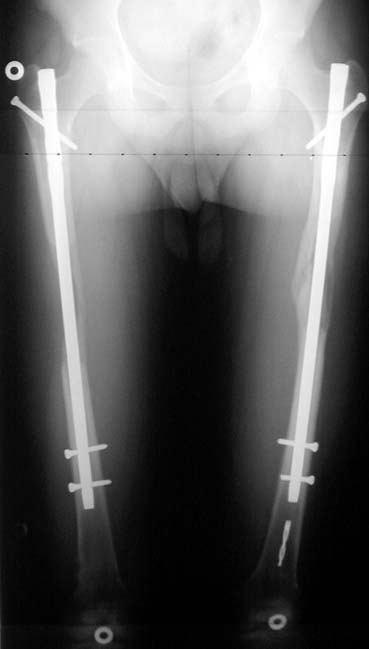

The patient lies is supine position at a traction table and legs are crossed with the uninvolved leg at the bottom. The medullary cavity is penetrated through piriform fossa using the standard method, and medulla is reamed 1.5 mm thicker than the nail to be used, over a guidewire. Proximal femur is reamed more, because the intramedullary nail is thicker proximally. The osteotomy site is planned at the X-Rays. It is important that at least 8 cm. of nail remains distal to the osteotomy site after the completion of the lengthening procedure. Percutaneous corticotomy is performed. The guide wire is advanced distally in order to measure the length of the nail. An intramedullary nail of apropriate length is placed. In the end, the nail is interlocked proximally, a suction drain is placed and the fist step of the operation is completed.

In selected cases, we prefer to use a combination of a unilateral dynamic axial fixator and an interlocked intramedullary nail, in order to protect the length and alignment after the completion of the lengthening procedure. As a prerequisite for this technique, the narowest diameter of the medullary cavity shall be wider than 7 mm and the length of the nail segment distal to the osteotomy site shall be at least 8 cm. after the completion of the lengthening procedure.The intramedullary nail neutralizes shear and bending forces on femur during lengthening, shortens external fixation time, and protects newly formed bone against fractures. In our series, subtrochanteric osteotomy was performed in one case. No varus angulation occured despite the intramedullary nail.

The combination of intramedullary anil and dynamic axial external fixator is harder as a technique than Standard Ilizarov applications. However, it is stil appealing due to the following advantages: shortening of the duration of external fixation, protection against refracture, early rehabilitation, gaining maximum range of motion and daily quality of life. These advantages are more important than disadvantages such as increased cost, increased blood loss and potetntial deep infection. All in all, we believe that the technique of femoral lengthening over an intramedullary nail is a safe and reliable method and provides advantages over standard Ilizarov aplications.